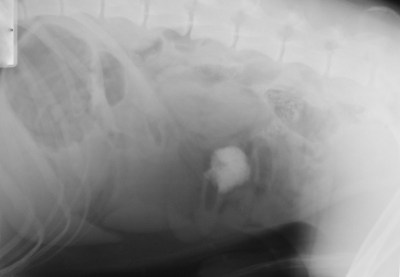

| Πλάγια ακτινογραφία κοιλίας στην οποία απεικονίζεται το ξένο σώμα (μπαλάκι) |

Το ξένο σώμα (λαστιχένιο μπαλάκι) αφαιρέθηκε από το λεπτό έντερο (νήστιδα) σκύλου φυλής

Σνάουζερ γιγαντόσωμης, ηλικίας 2 ετών, ο οποίος παρουσίαζε κατάπτωση, ανορεξία και εμέτους. Το μπαλάκι είχε καταποθεί περίπου 5 ημέρες πριν την επέμβαση και είχε προκαλέσει

πλήρη έμφραξη του εντέρου.